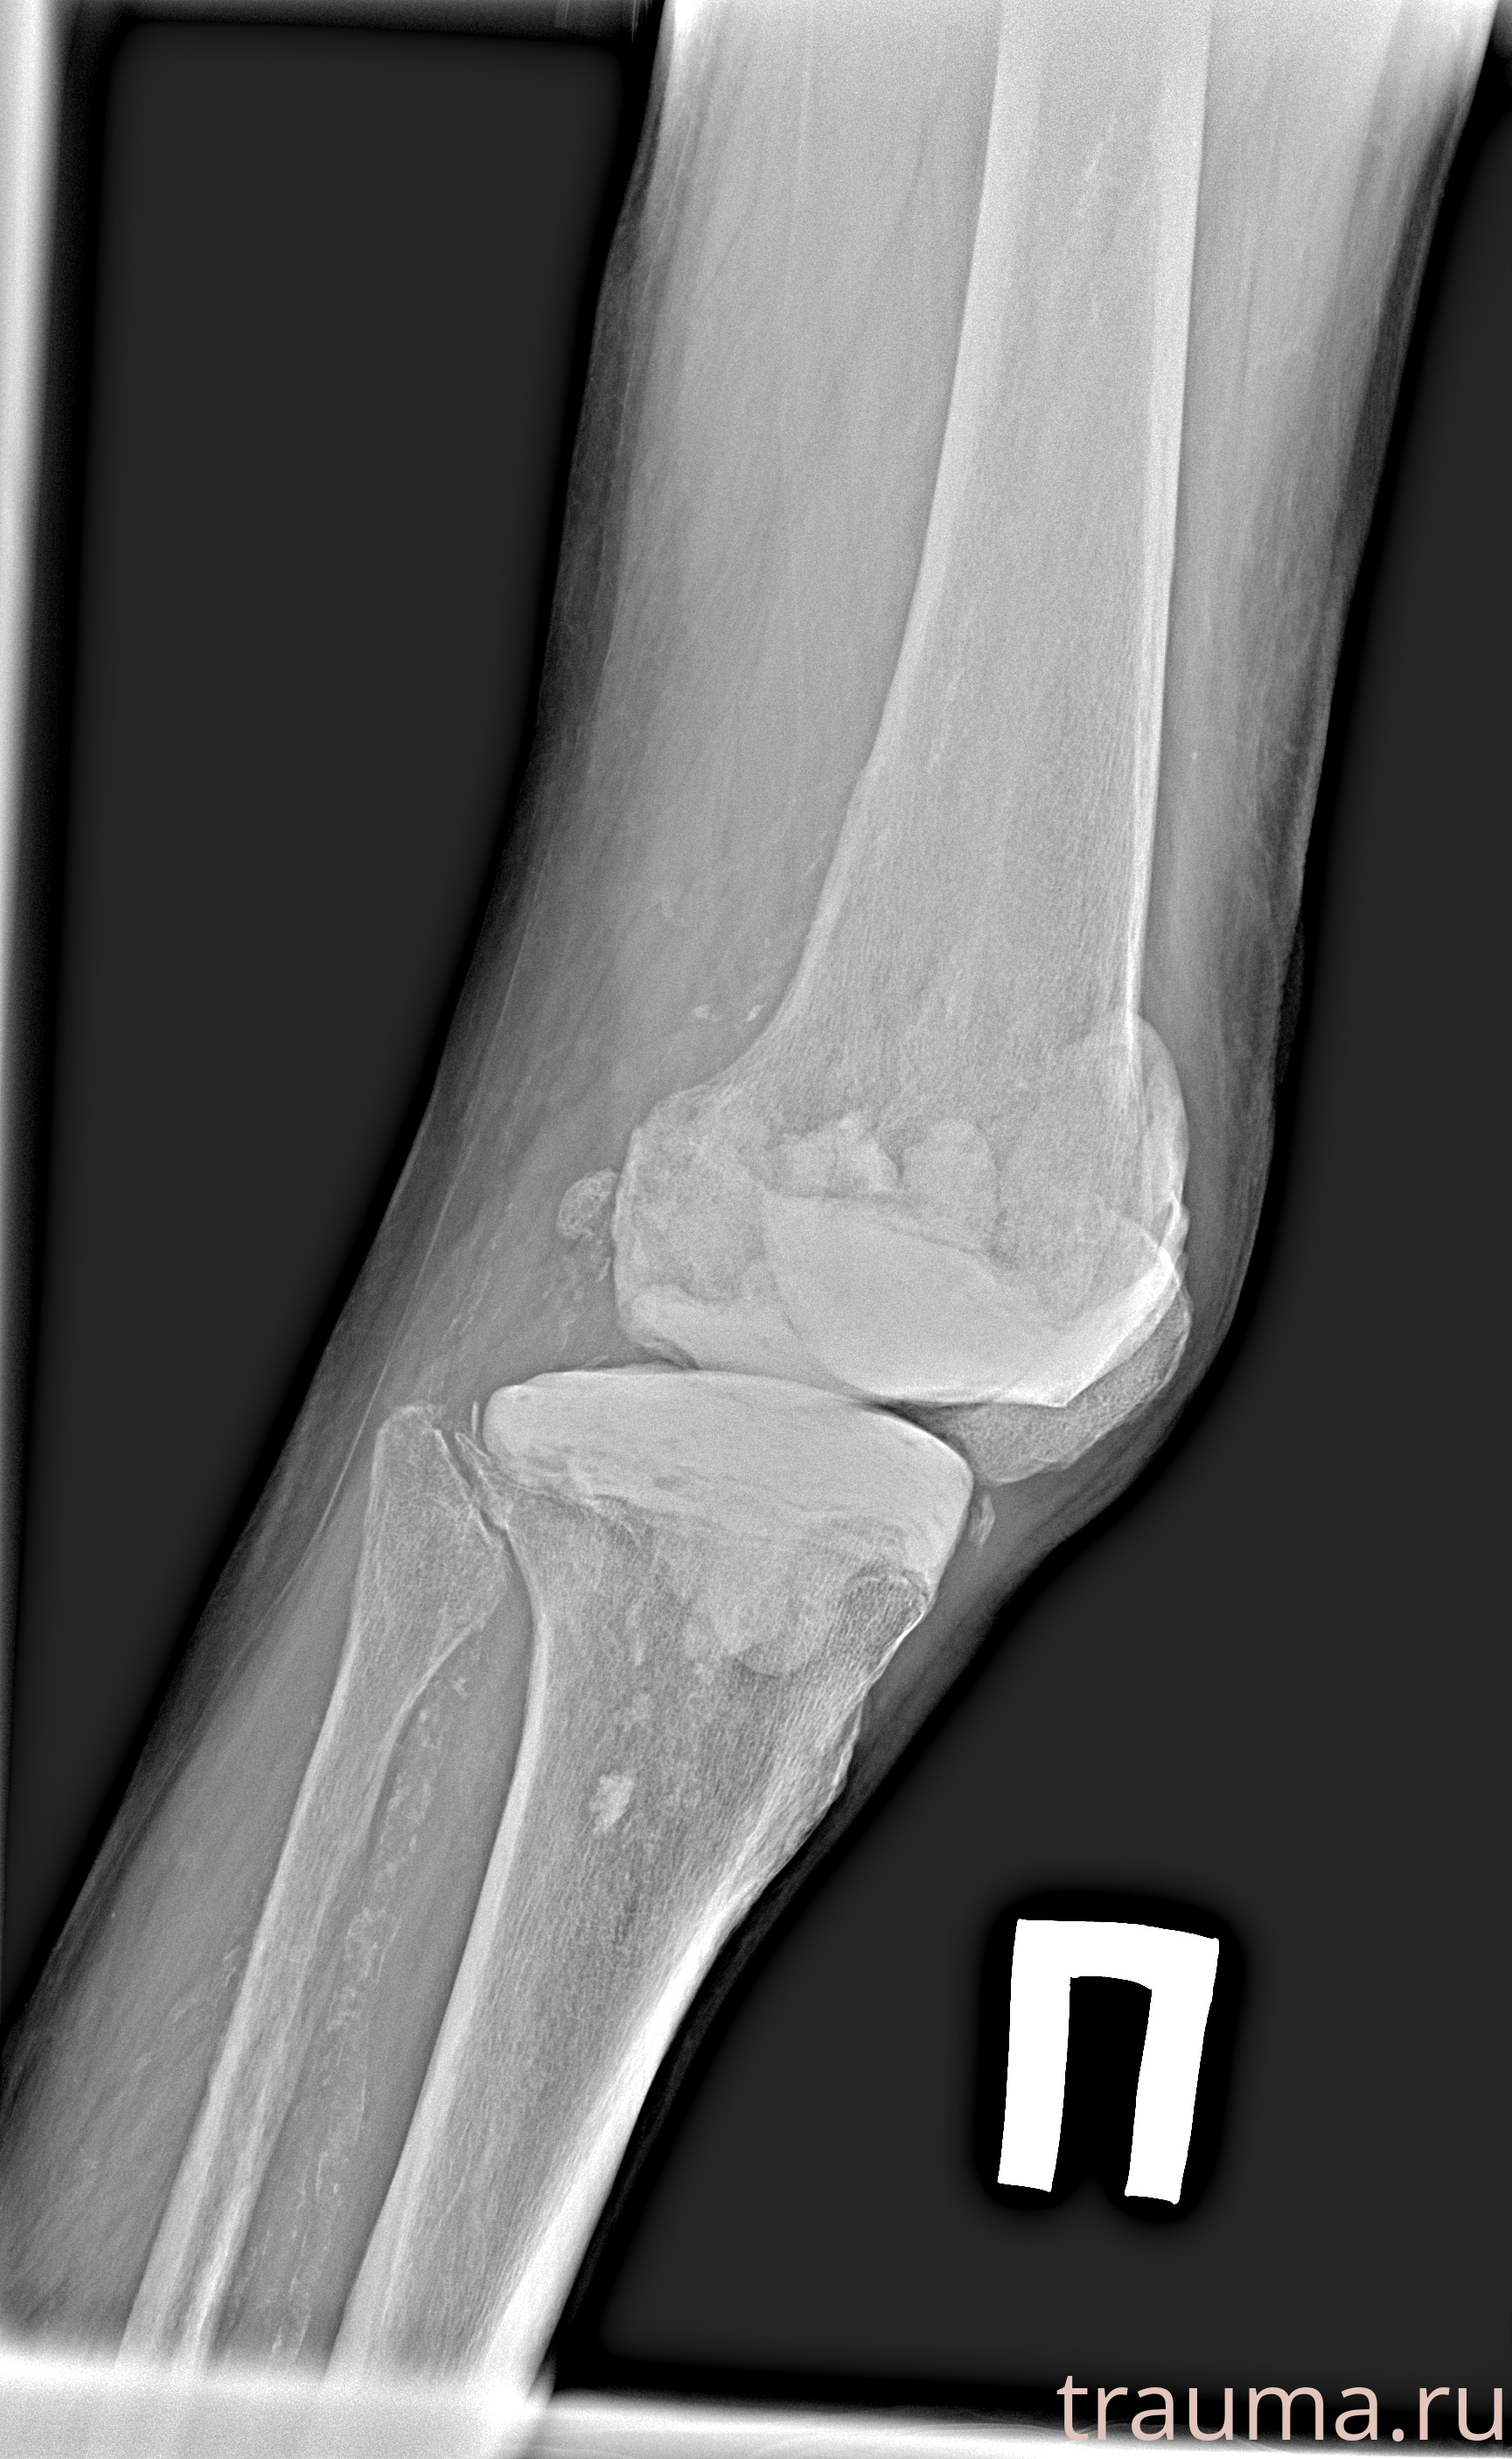

Рентген на дому: по вашему адресу приезжает врач-рентгенолог, травматолог-ортопед с мобильным рентгеновским аппаратом, проводит диагностику травмы или заболевания, делает необходимые рентгенограммы, дает рекомендации по дальнейшему лечению. Получить качественные снимки в домашних условиях возможно благодаря уникальной методике, разработанной МосРентген Центром для института  Склифосовского